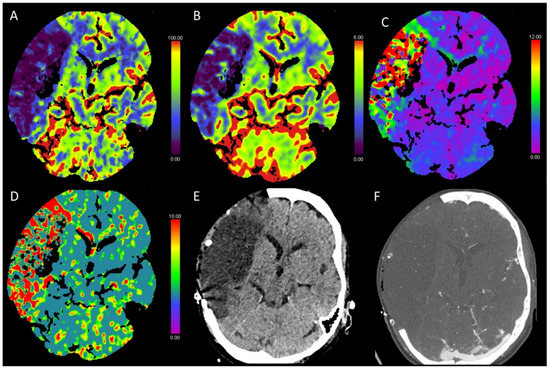

3.3. Global Hypoxic-Ischemic Injury/Brain Death